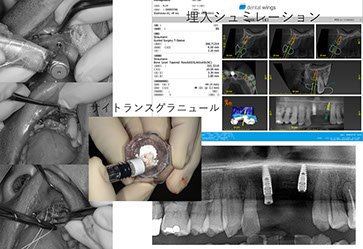

当院のインプラント治療はデジタルCTデータを基に専用ソフトにてインプラント手術をシミュレーションし、手術から最終補綴まで安心、安全そして長期安定性を目指し最新のプロトコルによるデジタルシステムで対応しています。また、骨の状態により骨増生、サイナスリフト、ソケットリフト、ボーンスプレッディング等、様々な対応をいたします。

当院で使用している骨補てん材は人体の骨と同じ成分の「炭酸アパタイト」が主成分で、患者さん自身の骨に緩やかに置換されます。国内では初めてインプラント埋入時での併用が認められましたsee more